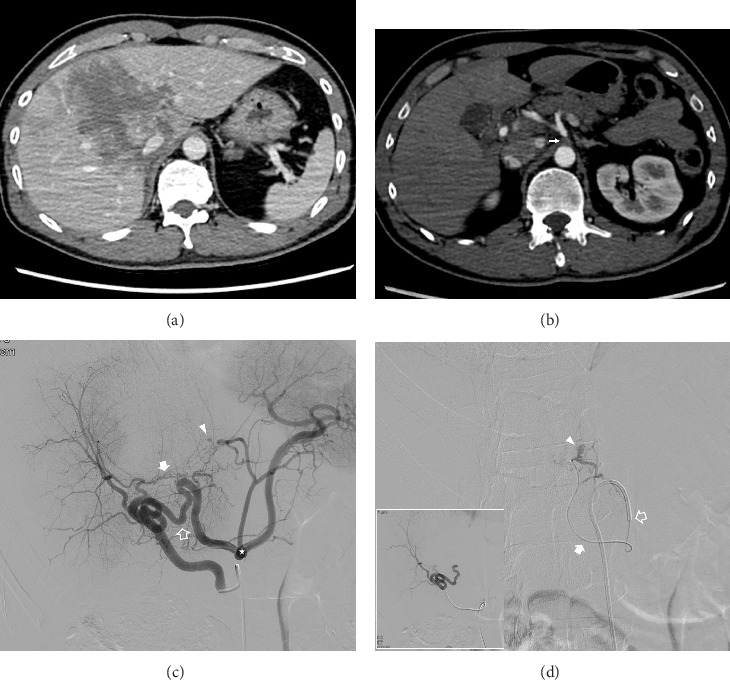

Purpose: This study aimed to evaluate the safety and efficacy of transcatheter arterial embolization (TAE) for hemorrhage control in patients with traumatic liver injury complicated by celiac axis stenosis (CAS). Methods: Nine patients diagnosed with CAS who underwent TAE between January 2012 and December 2024 were included in this retrospective study. Imaging studies were used to assess the vascular anatomy, and clinical outcomes were analyzed, focusing on technical and clinical success rates and complications. Results: All patients achieved technical success with TAE, with a clinical success rate of 77%, and no 30-day mortality. Seven patients had medial arcuate ligament compression, which was identified as the cause of CAS, while two patients had atherosclerosis. Conclusion: TAE is a safe and effective intervention for managing hemorrhage in traumatic liver injury complicated by CAS. Thorough assessment of computed tomography images is crucial for diagnosing the underlying causes of CAS and optimizing catheterization strategies.